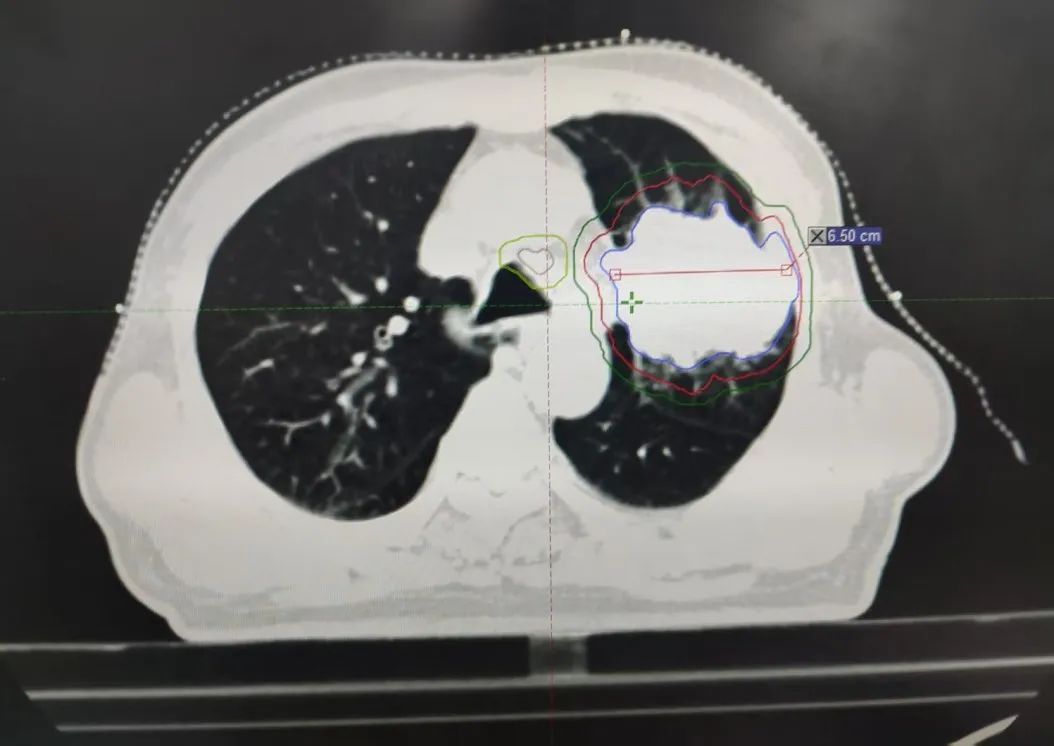

內(nèi)容提要 PART. 01 高齡抗癌的“生死抉擇” 當(dāng)6.7cm腫瘤遇上80歲身體 四年前,李大爺因乏力、消瘦、氣短等癥狀,意外發(fā)現(xiàn)左肺巨大占位,大小約6.7cm×4.9cm,最終在北京大學(xué)腫瘤醫(yī)院確診為肺鱗癌。面對(duì)82歲高齡和腫瘤的兇猛進(jìn)展,家屬一度陷入絕望,并決定回到家鄉(xiāng)醫(yī)院尋求治療方法。 治療前腫瘤影像 “開(kāi)胸手術(shù)風(fēng)險(xiǎn)極高,傳統(tǒng)化療對(duì)肺鱗癌效果有限,還可能加重身體負(fù)擔(dān)?!蓖醮簭?qiáng)主任回憶,團(tuán)隊(duì)當(dāng)即決定采用局部精準(zhǔn)放療,在確保療效的同時(shí),最大限度減少對(duì)正常組織的損傷,提高生活質(zhì)量,為老人開(kāi)辟一條生路。 PART. 02 四年抗癌“成績(jī)單” 腫瘤縮小70%,生活如常 治療的關(guān)鍵在于“毫米級(jí)”的精準(zhǔn)打擊。依托國(guó)內(nèi)頂尖放療設(shè)備——美國(guó)瓦里安直線加速器,團(tuán)隊(duì)通過(guò)三維適形調(diào)強(qiáng)放療技術(shù)(IMRT),將放射線誤差控制在1mm內(nèi),既集中火力攻擊腫瘤,又能降低周?chē)谓M織損傷。配合PET/CT生物靶區(qū)動(dòng)態(tài)追蹤技術(shù),醫(yī)生能清晰區(qū)分活躍癌細(xì)胞與壞死組織,實(shí)時(shí)調(diào)整治療方案。 四年間,李大爺?shù)哪[瘤病灶持續(xù)縮小,從最初的6.7cm縮小至目前的2.3cm,氣短癥狀顯著改善,治療期間甚至未出現(xiàn)放射性肺炎等并發(fā)癥。如今的他不僅生活完全自理,還活躍于社區(qū)老年活動(dòng),焦慮評(píng)分從重度降至幾乎消失。 治療后腫瘤影像 “很多患者以為抗癌就是‘你死我活’,其實(shí)‘帶瘤生存’同樣能創(chuàng)造生命價(jià)值。”這場(chǎng)“生命奇跡”的背后,是市二院放射治療中心對(duì)精準(zhǔn)醫(yī)學(xué)的深刻踐行,科室憑借超高的技術(shù)水平及一批國(guó)際頂尖設(shè)備支持,不斷提升生物靶區(qū)勾畫(huà)精度,并建立多學(xué)科診療(MDT)模式,融合外科、靶向、免疫、粒子等手段,為200余例高齡腫瘤患者制定個(gè)性化方案,顛覆了“高齡癌癥等于絕癥”的傳統(tǒng)認(rèn)知。 PART. 03 人民醫(yī)院 人民名醫(yī) 王春強(qiáng) 副主任醫(yī)師 ·葫蘆島市第二人民醫(yī)院放射治療中心主任 ·原中國(guó)人民解放軍第255醫(yī)院放射治療組組長(zhǎng) ·天津市第五中心醫(yī)院放射治療科主治醫(yī)師 ·中國(guó)抗癌協(xié)會(huì)會(huì)員 ·中國(guó)醫(yī)學(xué)繼續(xù)教育協(xié)會(huì)腫瘤放射治療專(zhuān)業(yè)委員 ·中國(guó)老年保健協(xié)會(huì)免疫健康管理專(zhuān)業(yè)委員會(huì)委員 ·中國(guó)老年保健協(xié)會(huì)多學(xué)科診療專(zhuān)業(yè)委員會(huì)委員 ·遼寧省免疫學(xué)會(huì)腫瘤營(yíng)養(yǎng)與免疫分會(huì)委員會(huì)委員 專(zhuān)業(yè)特色: 從事腫瘤放射治療近20年,曾于空軍總醫(yī)院進(jìn)修腫瘤放射治療學(xué)。擅長(zhǎng)頭頸部腫瘤、胸腹部腫瘤、盆腔腫瘤等腫瘤多發(fā)、疑難病診治。精通三維適形放射治療(3DCRT)、調(diào)強(qiáng)放射治療(IMRT)、圖像引導(dǎo)放射治療(IGRT)、容積旋轉(zhuǎn)調(diào)強(qiáng)放射治療(Rapid-Arc)、SBRT、VMAT等先進(jìn)放療技術(shù)。尤其擅長(zhǎng)中樞神經(jīng)系統(tǒng)腫瘤、鼻咽癌、宮頸癌、直腸癌、食管癌、肺癌、腦轉(zhuǎn)移、骨轉(zhuǎn)移、淋巴結(jié)轉(zhuǎn)移、肺轉(zhuǎn)移、肝轉(zhuǎn)移等腫瘤的放療,尤其對(duì)部分腫瘤的疑難雜癥的處理積累了豐富的經(jīng)驗(yàn)。熟練掌握頭頸部及體部腫瘤的影像診斷及綜合治療原則,注重規(guī)范化治療。擅長(zhǎng)為腫瘤患者制定個(gè)體化治療方案。